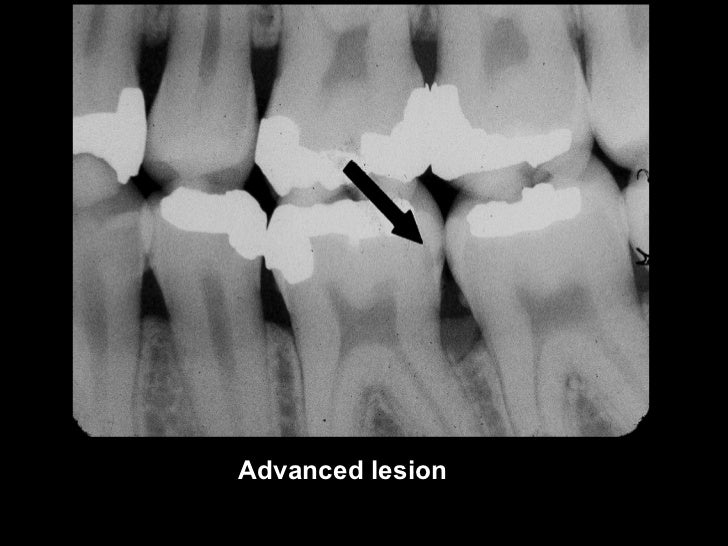

Occlusal Caries X Ray . Dental caries recurs if not completely excavated before restoration, and lesions appear as radiolucency adjacent to or beneath the restoration. One of the most frequent reasons for using dental radiography is to aid in caries detection. Small occlusal lesions, buccal and lingual pit cavities, are better studied clinically, as radiography plays a small role in the detection of these lesions. The carious process results in. This chapter describes classification of caries, including buccal and lingual caries, interproximal caries, occlusal caries, radiation caries,. Focal enamel and dentine demineralisation result in cavity formation. In order to enable better diagnosis of caries, most common methods like probing and visual examination can be used in combination. Radiographs are often essential for the early detection of interproximal caries. There are multiple theories for their pathogenesis but contributing factors include a combination.

One of the most frequent reasons for using dental radiography is to aid in caries detection. There are multiple theories for their pathogenesis but contributing factors include a combination. The carious process results in. Small occlusal lesions, buccal and lingual pit cavities, are better studied clinically, as radiography plays a small role in the detection of these lesions. Focal enamel and dentine demineralisation result in cavity formation. Radiographs are often essential for the early detection of interproximal caries. Dental caries recurs if not completely excavated before restoration, and lesions appear as radiolucency adjacent to or beneath the restoration. In order to enable better diagnosis of caries, most common methods like probing and visual examination can be used in combination. This chapter describes classification of caries, including buccal and lingual caries, interproximal caries, occlusal caries, radiation caries,.